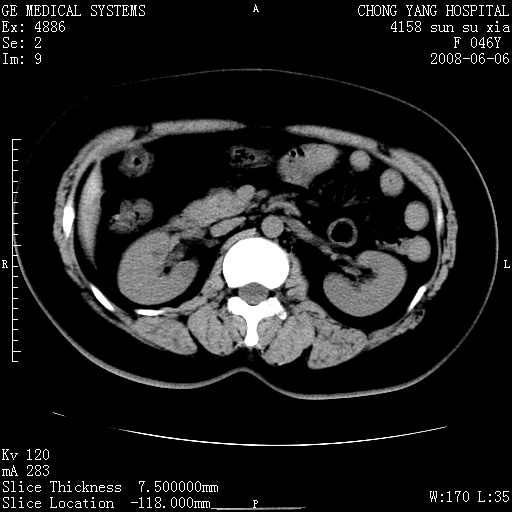

标题: CT13886:F 40Y, 外侧的CT值-60 内侧的25HU. 未作增强 [打印本页]

标题: CT13886:F 40Y, 外侧的CT值-60 内侧的25HU. 未作增强

考虑:右肾错构瘤。

右肾平滑肌脂肪瘤并肾囊肿

右肾血管平滑肌脂肪瘤并肾囊肿(后者请排除容积效应,可结合超声)

右肾血管平滑肌脂肪瘤并肾囊肿(后者请排除容积效应,可薄层扫描或结合超声)

根据影像表现,基本可确诊!